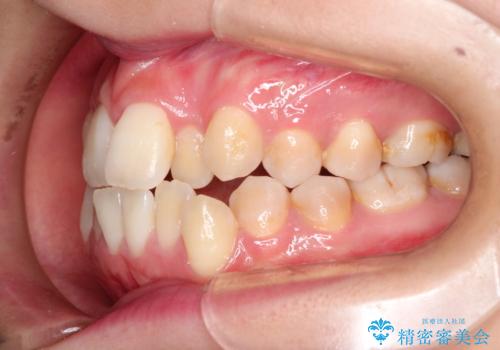

- 前歯のガタガタと、かみ合わせを改善したいとのことで来院されました。

人前でお話をするお仕事のため、装置をつけないでよいマウスピース矯正を希望されました。

下顎の歯が、上顎の歯に対して前方に位置していたので、下顎の歯を後方に移動させるのと、歯と歯の間を削りスペースを作り、歯を並べる計画としました。